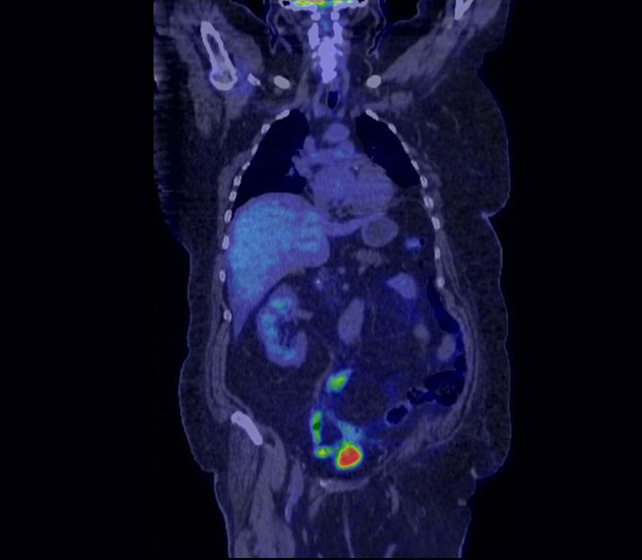

Le TEP SCAN (Tomographie par Émission de Positons) ou PET SCAN est une technique d’imagerie fonctionnelle qui utilise principalement comme traceur le FDG (FluoroDeoxyGlucose), analogue du sucre, qui a pour caractéristique d’aller se fixer préférentiellement sur les cellules tumorales, permettant ainsi de les repérer.

En cancérologie, cet examen a connu un essor important. Couplé au scanner, il est utilisé entre autre pour réaliser le bilan d’extension de tumeurs diverses, mais aussi pour évaluer la réponse thérapeutique par exemple au décours de chimiothérapie ou de radiothérapie.